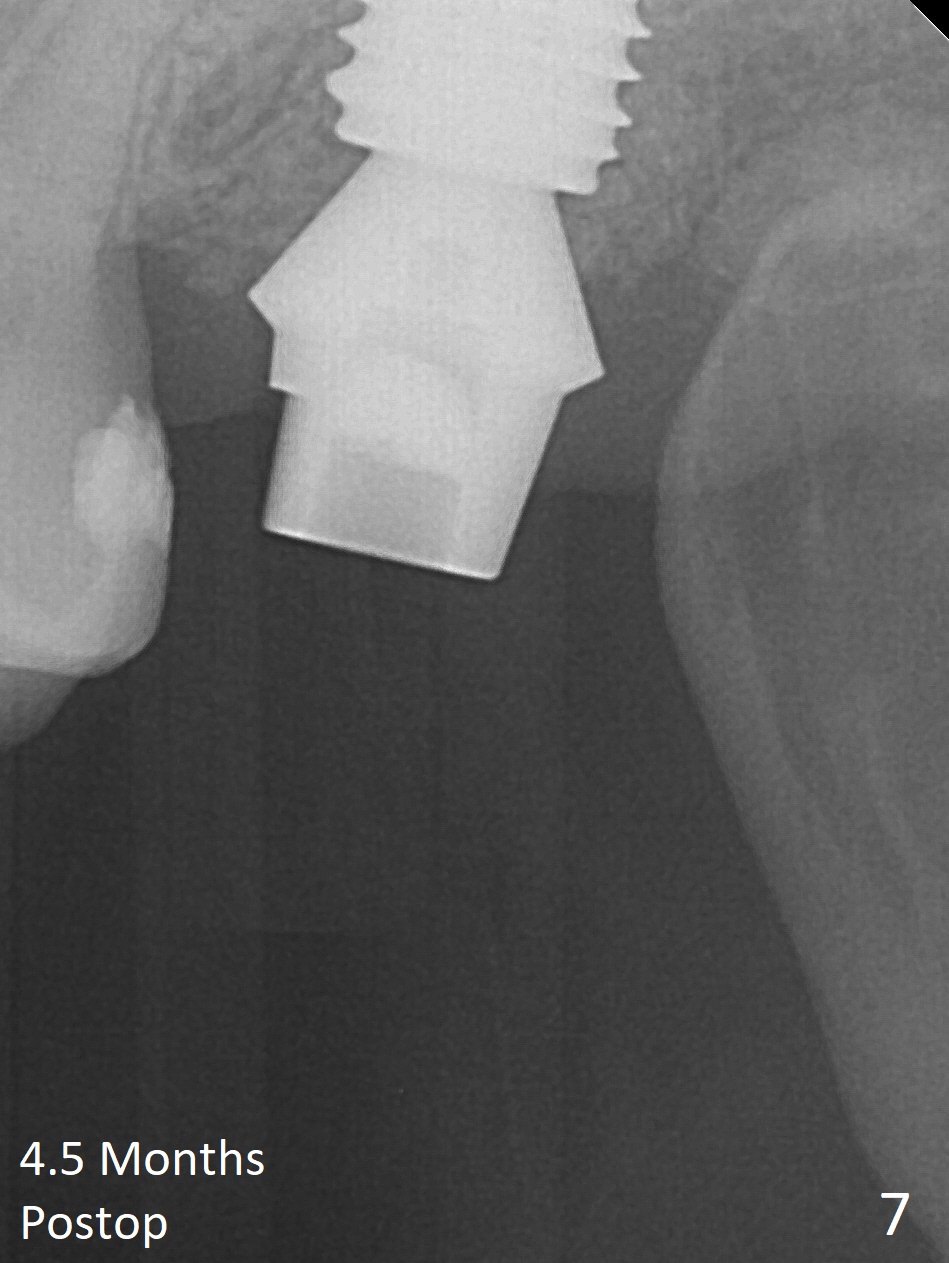

Implant Longer than Planned

While the tooth #2 has a mesiodistal crack line with symptom (Fig.1 arrowheads, crown pending), the tooth #15 has a mesiodistal fracture (Fig.2). Immediately preop 5x5 cm CBCT (Fig.3) confirms the palatal (P) fracture with palatal bone loss. Although a 5x7.3 mm implant fits the site by design (Fig.4), a much longer implant is required to achieve primary stability past the sinus floor using IBS Magic Expanders (Fig.5,6 (20-30 Ncm; sinus lift with PRF membrane and allograft)). In contrast, primary stability could not be obtained by engaging dummy implant to the socket walls. A short implant without sinus lift is associated with less obvious complication such as fibrointegration. The implant seems osteointegrated 4.5 months postop (Fig.7). The abutment is changed to 6.5x4(5) mm before impression. There is no bone loss 5 months post cementation (Fig.8 (11 months postop)). It is the same 2.5 years post cementation (Fig.9,10).